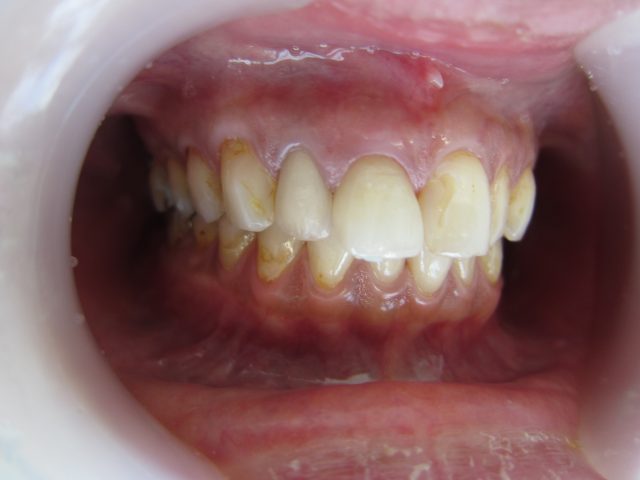

術前

上の前歯の先端が変色しており、歯並びも出っ歯のようになっています。

ラミネートベニア合計8本で形と色を整えました。